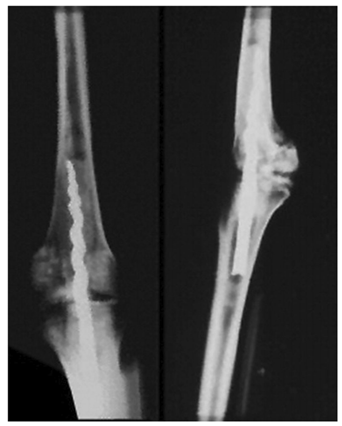

Ce fut le cas de la momie appelée Usermontu trouvée dans la tombe de Toutankhamon, où un clou fileté était inséré entre le fémur et le tibia pour stabiliser l'articulation du genou (comme sur la figure 2).